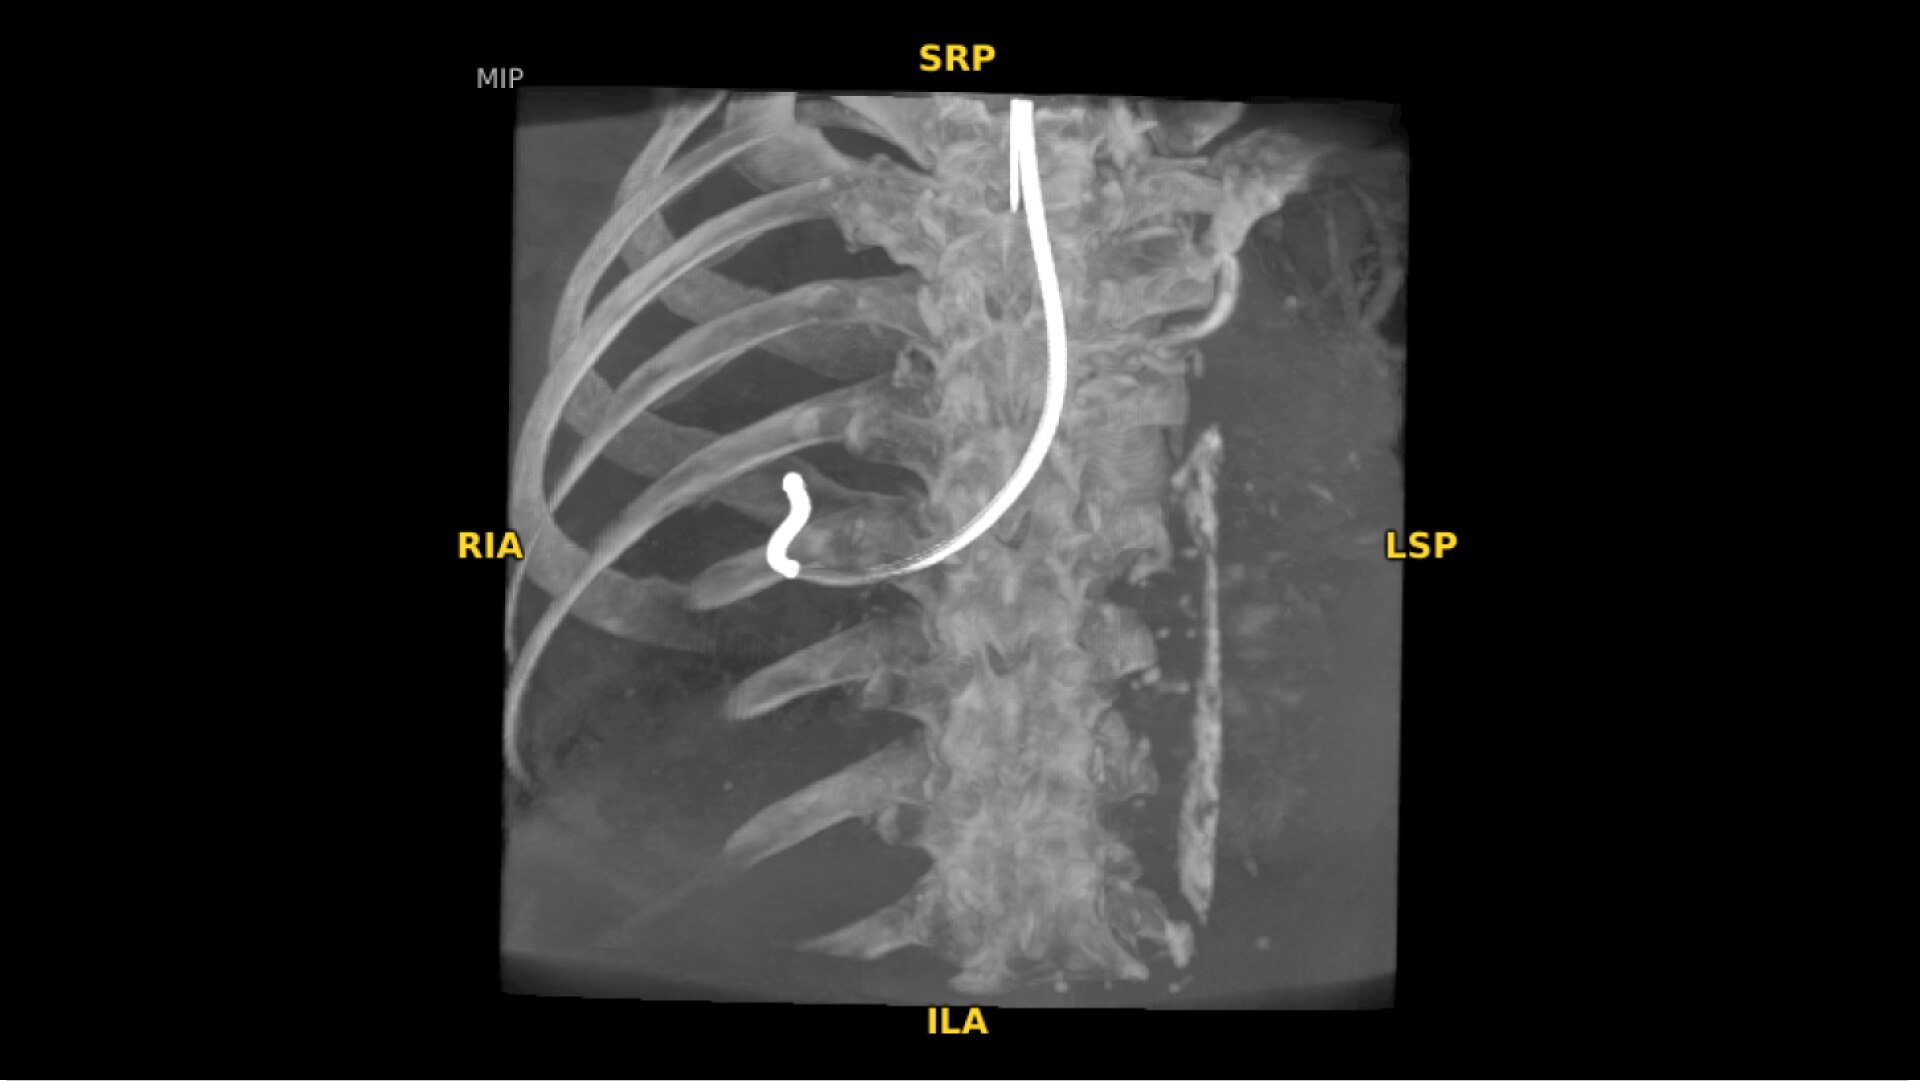

A 3D C-arm for every day:  from spinal fusion or orthopedic fractures to angiogram and stent placement

True 3D and 2D imaging flexibility. Transitioning quickly and easily provides greater efficiency and versatility for a wide range of clinical applications from spine and orthopedics to cardiac and vascular. Finally, a 3D C-arm that every surgical suite deserves.

Enhance intraoperative decision-making with visualization capabilities of Augmented Fluoroscopy in the OEC 3D Volume Viewer. Analyze five perspectives with 3D imaging tools including Multi-Oblique Mode, scrolling 512 slices, zoom, and more.